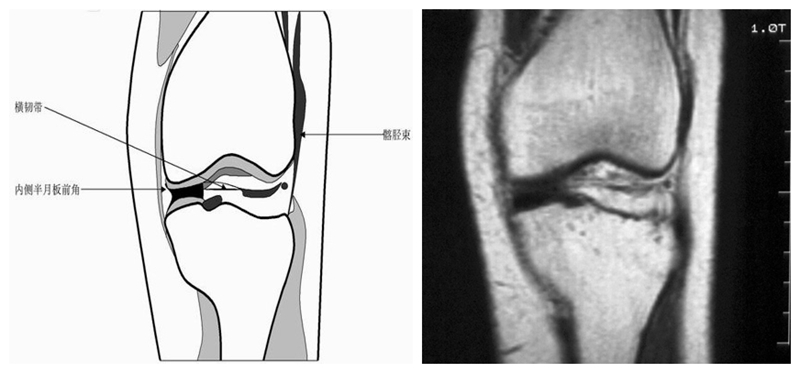

膝关节冠状面MRI解剖

显示内外侧副韧带、腘肌和拱状韧带,有无信号和结构改变,侧重关节胫股软骨的两边和半月板的体部。

冠状位解剖第四层